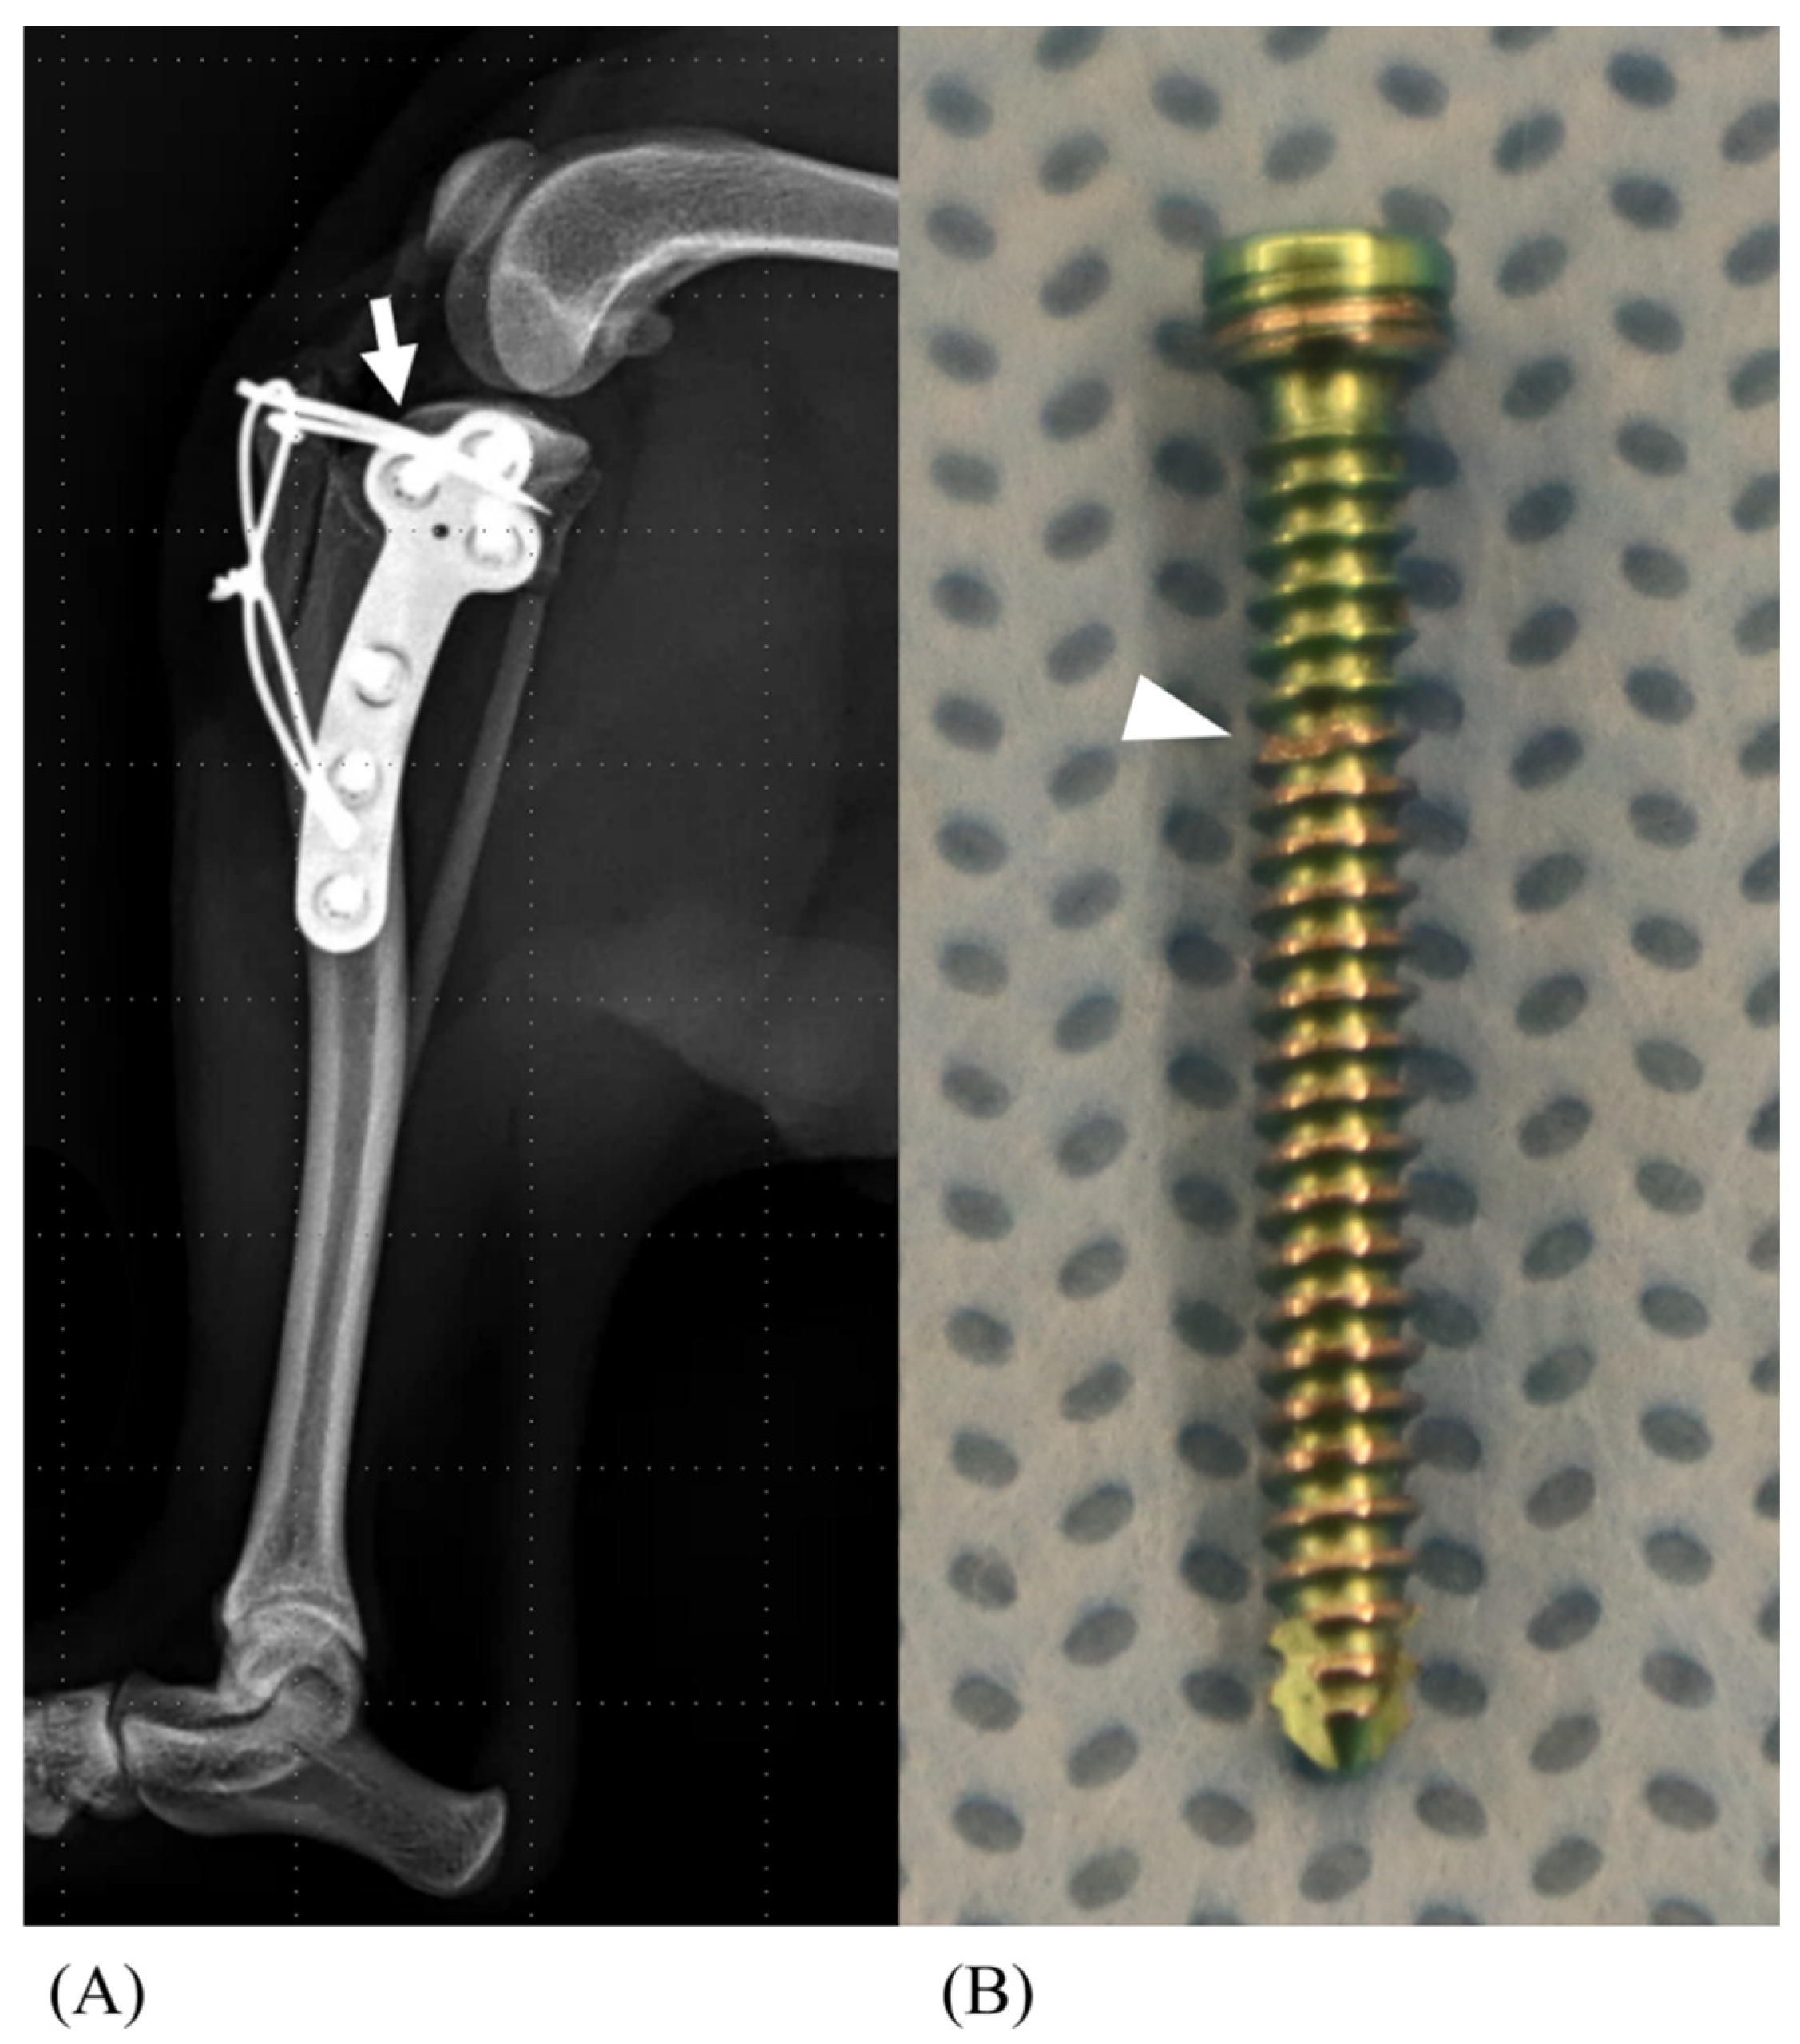

2.2. Surgical Techniques

- Hawbecker, T.J.; Duffy, D.J.; Chang, Y.J.; Moore, G.E. Influence of Kirschner-Wire Insertion Angle on Construct Biomechanics following Tibial Tuberosity Osteotomy Fixation in Dogs. Vet. Comp. Orthop. Traumatol. 2023, 36, 75–81. [Google Scholar] [CrossRef]